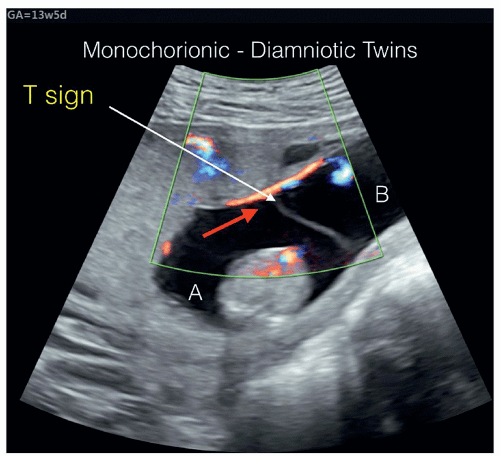

We associate pregnancy with a growing tummy. Figure 2 From Monochorionic Diamniotic Twin Pregnancies Natural History And Risk Stratification Semantic Scholar

Figure 2 From Monochorionic Diamniotic Twin Pregnancies Natural History And Risk Stratification Semantic Scholar from d3i71xaburhd42.cloudfront.net